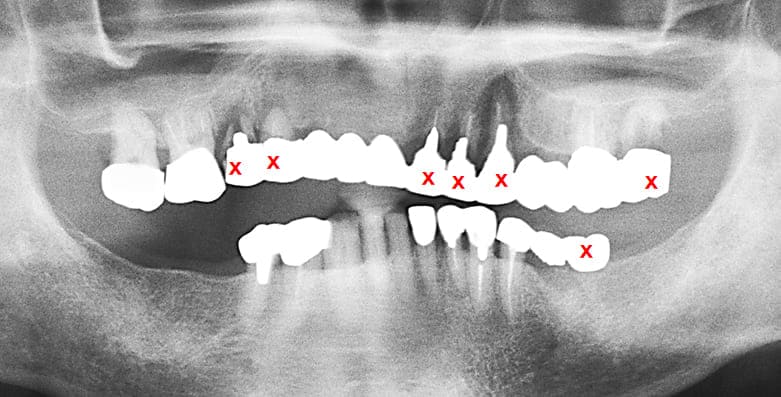

治療計画

- 保存できない両側上下臼歯(残根)を抜歯

- 上顎の前歯部分に関しては温存できない#12,13を抜歯。温存できると思われる#11,21,22を支台としてブリッジ仮歯を入れ、抜歯後の治癒を待つ

-

両側上顎臼歯部にインプラントを埋入

両側臼歯部の咬合の再構築Vertical Stopが完成してから前歯部のインプラント埋入を行う